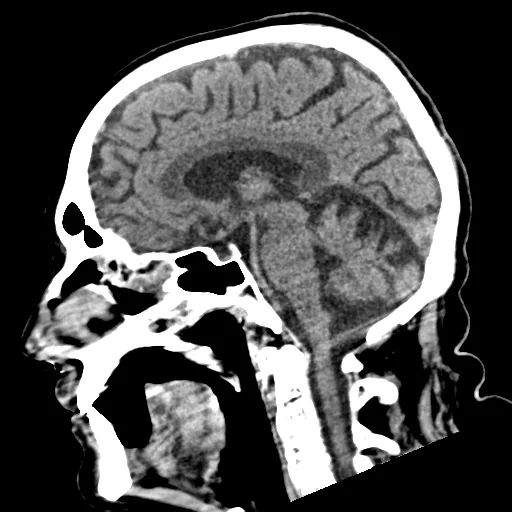

Marchiafava-Bignami病

Marchiafava-Bignami病(MBD)是一种罕见的中枢神经系统紊乱,通常在酗酒和营养不良的情况下出现。涉及到胼胝体的坏死和脱髓鞘。

这种疾病归因于缺乏维生素B,并导致坏死和脱髓鞘,特别是胼胝体。

CT

胼胝体在急性期可出现水肿,慢性期可出现萎缩性。